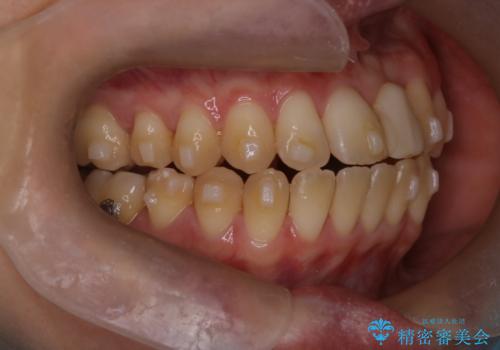

前歯の開咬とシザーズバイトを改善|インビザライン矯正

- 治療計画

前歯が噛まないため咀嚼が困難で、シザーズバイトにより噛み合わせに不調を感じていました。インビザラインを用いて、透明なマウスピースによる目立ちにくい矯正治療を実施。奥歯のシザーズバイトを改善した後、前歯の歯列を緻密に調整し、噛み合わせを整えました。定期的なマウスピース交換を通じて徐々に歯列が改善され、治療終了後には前歯が正常に咬合するようになり、噛み合わせの機能性と審美性が共に向上しました。